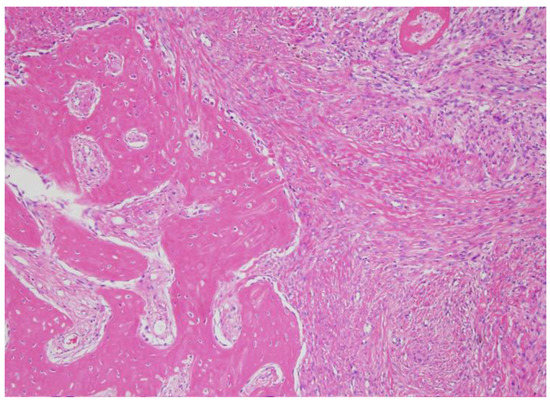

2.3. Diagnosis and Management